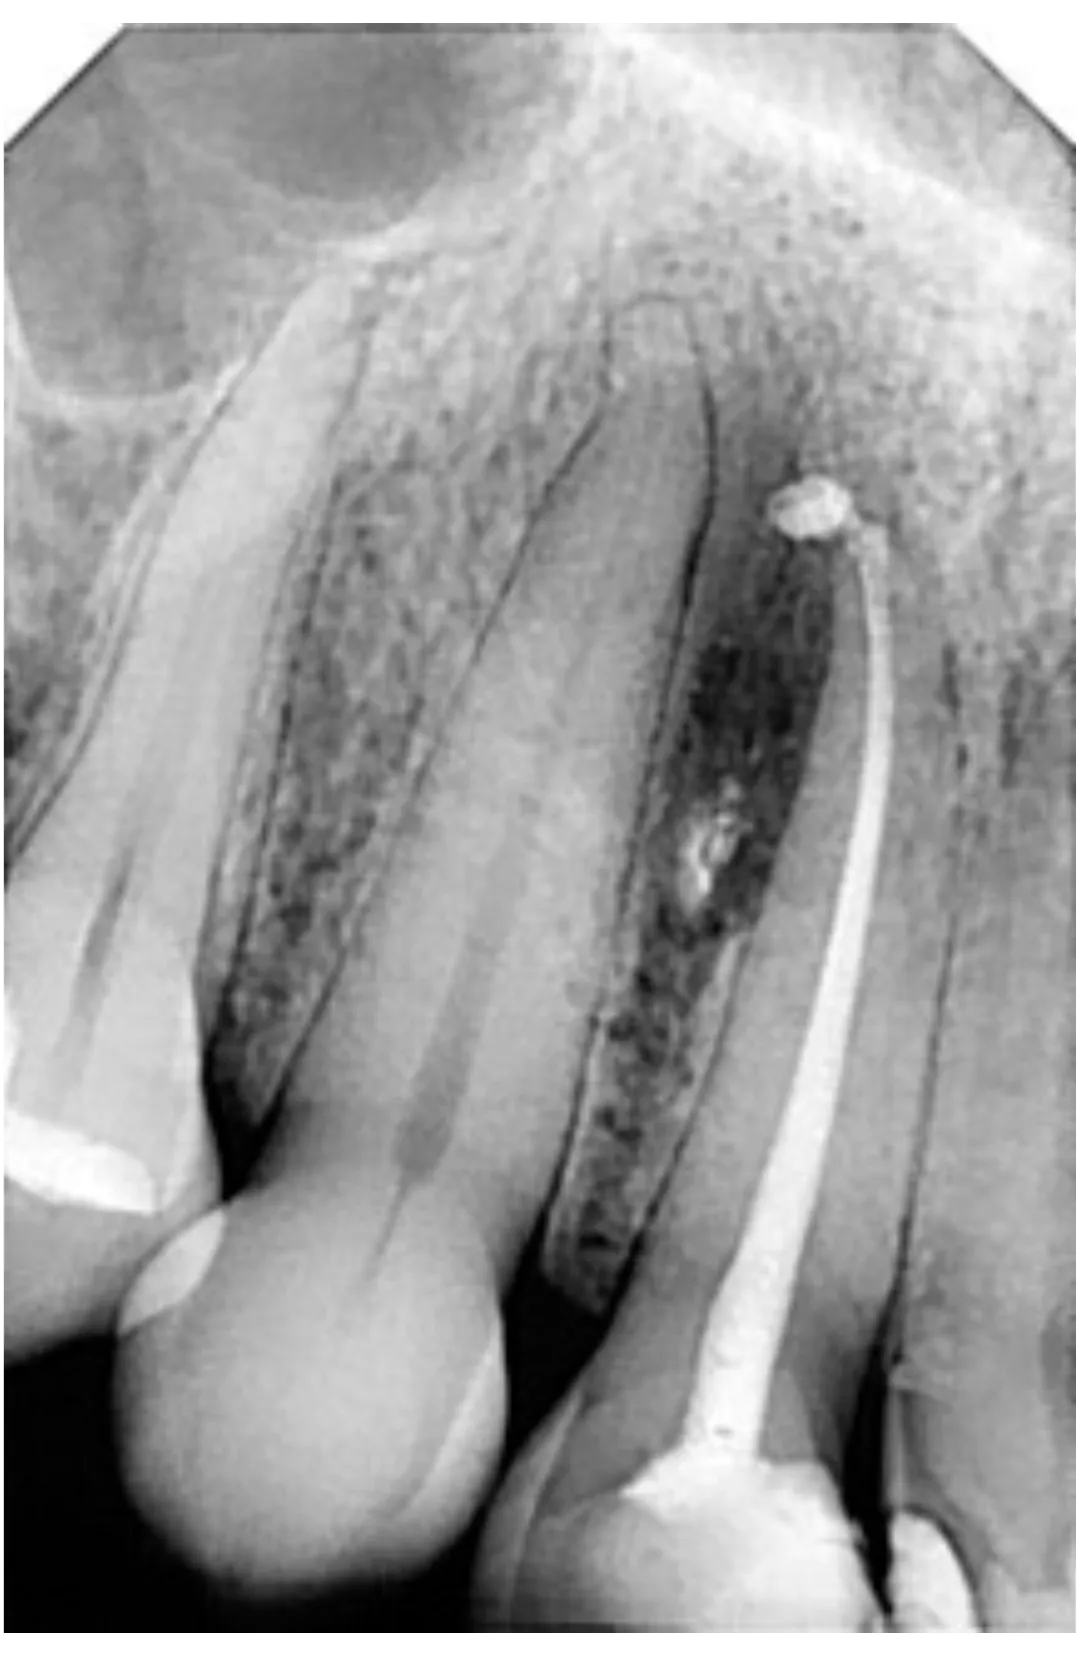

RXDC efikasnost proizlazi iz kombinacije napredne tehnologije i izvanredne sposobnosti za proizvodnju slika visoke definicije. RXDC X- ray uređaj pruža vrhunske performanse, praktičnost i tehnologiju. RXDC se odlikuje generatorom konstantnog potencijala visoke frekvencije (DC) i vrlo malom fokalnom tačkom (0,4 mm) koja omogućava oštre i detaljne slike, istovremeno osiguravajući radnu udobnost i niske doze zračenja za pacijenta.

Veće performanse sa RXDC, rendgenskim uređajem koji kombinuje slike visoke definicije, ergonomski dizajn i niske doze zračenja.

SUPERIORNA DIJAGNOSTIČKA KVALITETA Dobijena u samo nekoliko jednostavnih koraka, sve slike su visoke rezolucije.

NAPREDNA TEHNOLOGIJA

NewTom RXDC rendgenski uređaj visoke frekvencije baziran je na NewTom-ovom znanju, sa udaljenošću izvora od 30 cm i fokalnom tačkom od 0,4 mm.

MINIMALNA DOZA ZRAČENJA

Zahvaljujući pravougaonom kolimaciji i ECO Mode parametrima,

izloženost pacijenta X-zracima je minimalna.